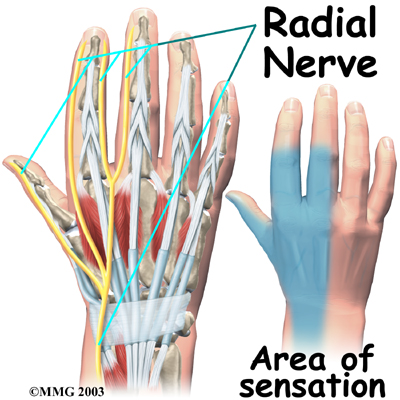

The runs along the thumb-side edge of the forearm. It wraps around the end of the radius bone toward the back of the hand. It gives sensation to the back of the hand from the thumb to the third finger. It also supplies the back of the thumb and just beyond the main knuckle of the back surface of the ring and middle fingers.

The nerves that travel to the hand are subject to problems. Constant bending and straightening of the wrist and fingers can lead to irritation or pressure on the nerves within their tunnels and cause problems such as pain, numbness, and weakness in the hand, fingers, and thumb.